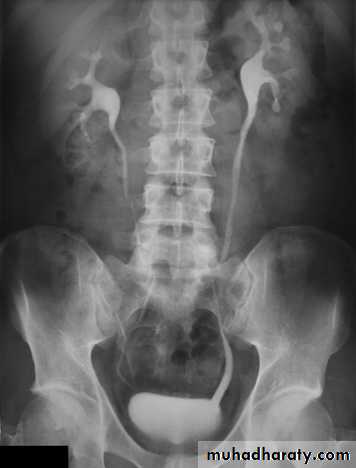

Normal IVU series

Failure of contrast to pass to ureters due to both sided mid ureteric stones

LT sided upper Ureteric stones

Bilateral HU + HN